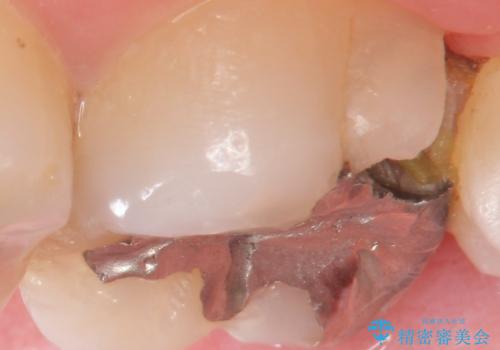

- 定期検診を希望され来院、虫歯が発見されたため治療へと移行しました。

虫歯の大きさや残存歯質・窩洞形態によりゴールドやセラミックといった材質を選択することでより歯を削る量を少なくすると同時に強度も確保、長期的な予後を期待できるような治療を実践していきます。

今回の治療では、虫歯を除去したのちより修復に適した素材を選択することで歯を削る量を可及的に少なくすることと、長期的な予後を期待できるような状態にすることができました。